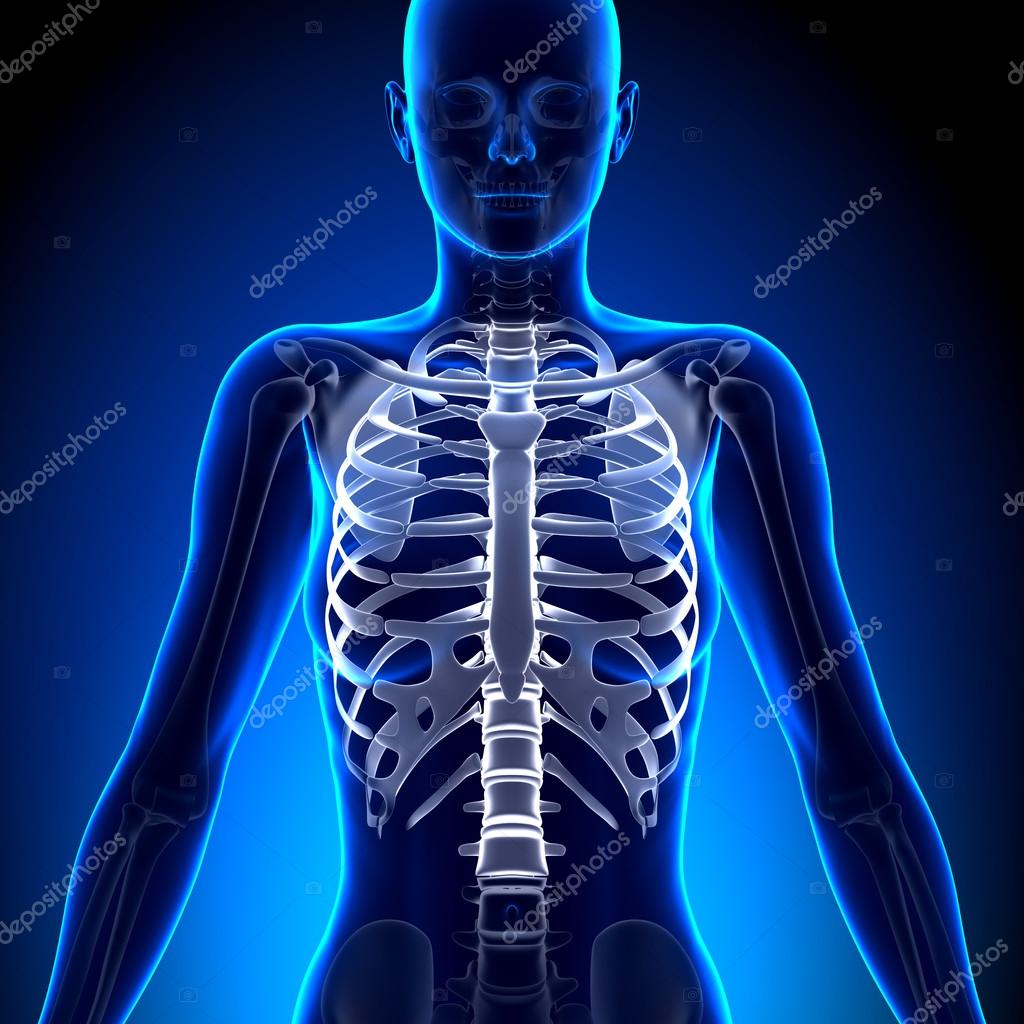

Female Rib Cage Anatomy Bones Stock Illustration

Female Rib Cage Anatomy Bones Stock Illustration

Female Upper Body Bones Computer Illustration Stock Photo

Female Upper Body Bones Computer Illustration Stock Photo